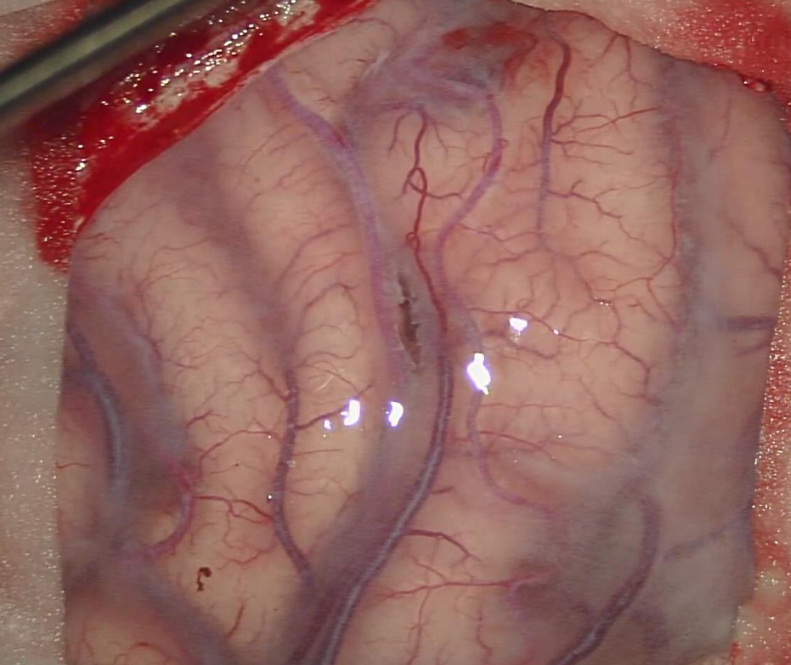

打开硬膜以后,发现脑皮层动脉萎缩变细:

基本都达不到1mm。